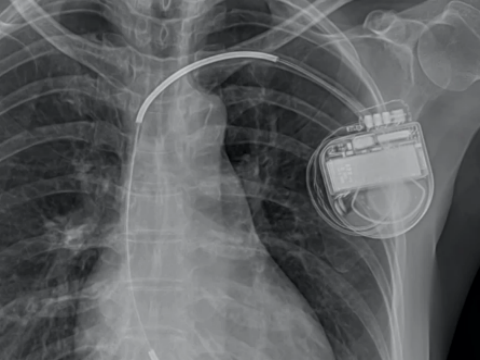

Công nghệ truyền năng lượng quang tử hoạt động sử dụng ánh sáng để sạc điện cho thiết bị cấy ghép